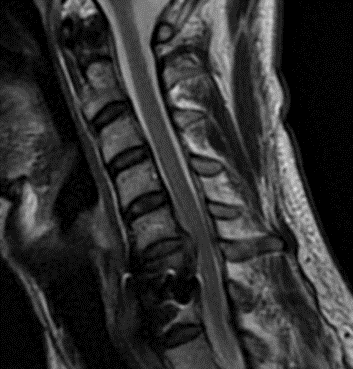

He had no neurologic deficits on exam, and therefore was started on a trial of multidisciplinary and multimodal conservative management. This included non-opioid pharmacologic regiment, lifestyle modification, physiotherapy, chiropractic, and epidural steroid injection. Despite these conservative measures, his symptoms remained severe and debilitating, and therefore surgical options were discussed. He underwent an uneventful C5-6 anterior artificial disc replacement. Postoperatively, his neck and radicular arm pain had fully resolved. Imaging demonstrated maintained physiologic flexion and extension of the cervical spine (Figure 2). This motion-preserving surgery reduces the adjacent degeneration process, and the need for further surgeries down the line.

Figure 2: Postoperative dynamic xrays; note the differences in range of motions between the artificial disc at C5-6 and the previous fusion at C6-7.